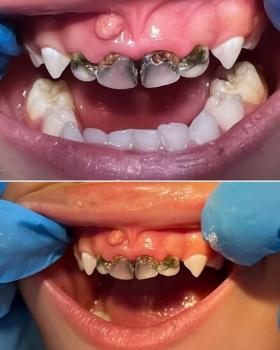

Getting a dental implant after a tooth extraction is one of the most common questions patients ask. The timing depends on your healing, bone condition, and overall oral health.